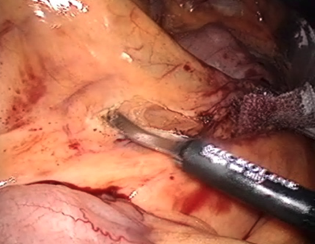

大腸についている血管の入った膜(腸間膜といいます)を切り開き、腸に行く血管を処理する(切り離す)準備をします。

もともととても粗くくっついている膜なので、ほとんど血が出ることなく、この膜をはがすことができます。

もともととても粗くくっついている膜なので、ほとんど血が出ることなく、この膜をはがすことができます。腸間膜の中の血管